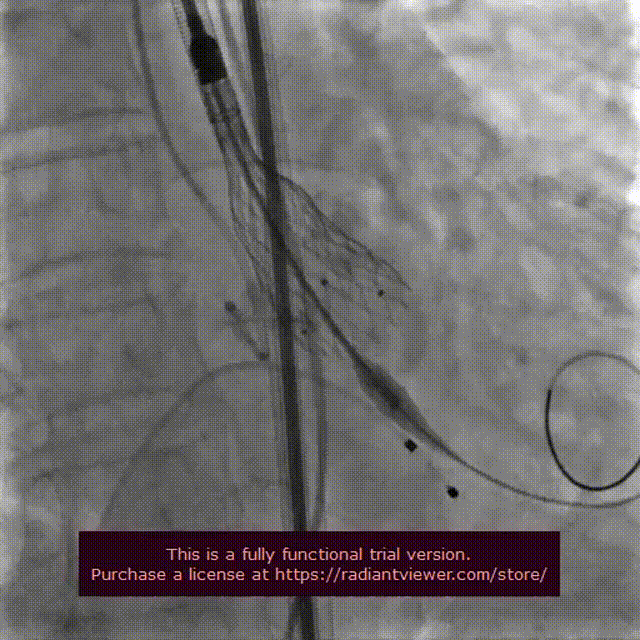

VenusA-Plus®释放过程

18 mm球囊后扩

瓣膜完整形态

术者团队观察到瓣膜形态未能完全伸展,为取得更好治疗效果,后续予以后扩处理。采用18 mm球囊进行后扩后扩,行主动脉造影提示瓣膜置入位置良好、形态完整。